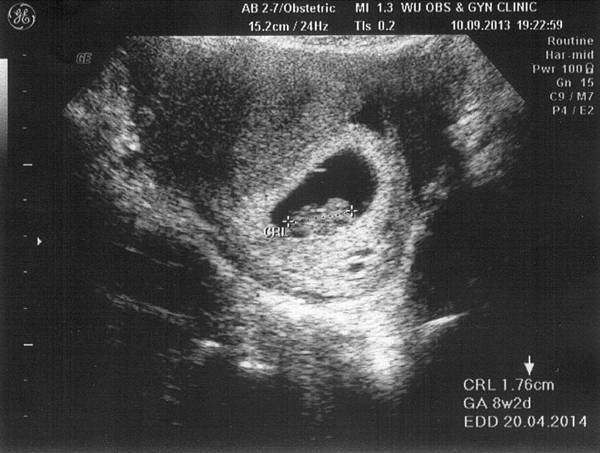

• 9月 11 週三 201311:59

1234591_10201768014351894_723686032_n.jpg4w4d.jpg8w2d-1.jpg8w2d-2.jpg

(繼續閱讀...)